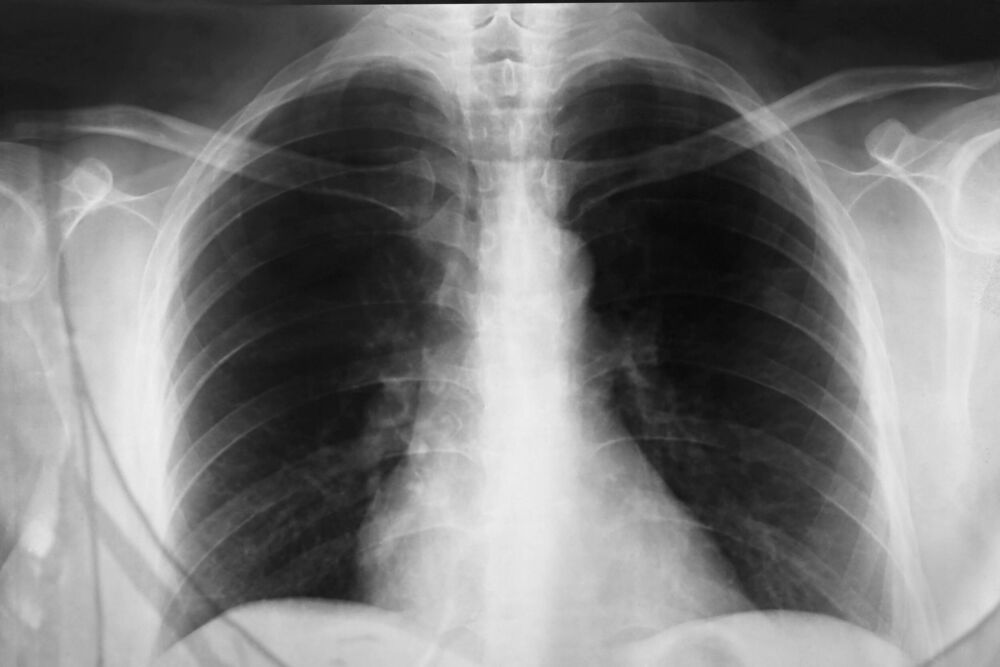

Svi navedeni razlozi mogu da budu direktni izazivači nadražajnog kašlja, koji, prema rečima stručnjaka, ne bi trebalo da traje duže od tri nedelje, jer nakon toga treba uraditi kompletan pulmološki pregled. Ono što je najvažnije, to je da se hitno pronađe uzrok i uzme prava terapija kako bi se sprečile moguće komplikacije.

Direktor Klinike za pulmologiju KCS dr Mihailo Stjepanović objašnjava da velike temperaturne razlike ne prijaju našim plućima, jer kada izađemo iz rashlađenog prostora na toplo, može se javiti spazam disajnog puta, što može biti i jedan od razloga za kašalj.